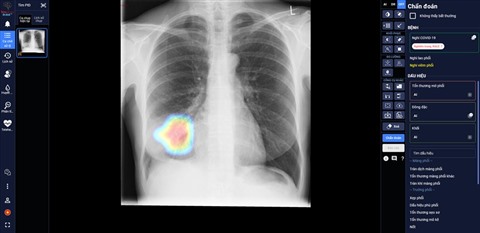

| DrAid aide les médecins à surveiller les lésions pulmonaires chez un patient F0 sur une radiographie pulmonaire. |

Il s'agit d'un nouvel outil pour soutenir le dépistage et le pronostic des traitements du COVID-19, contribuant à une prévention et à un contrôle efficace de la maladie.

Après plus d'un an de recherche, VinBrain a officiellement achevé le produit DrAid avec la capacité de résoudre, de manière générale, le problème de COVID-19, de l'aide au diagnostic au pronostic de traitement basé sur des images, notamment.

À ce jour, le modèle de DrAid dispose de la plus grande source de données au monde sur le COVID-19, dont 21.421 images radiographiques thoraciques de patients positifs au SARS-CoV-2 et 118.018 images radiographiques thoraciques standards.

Dans les hôpitaux acceptant le traitement COVID-19, DrAid soutient les médecins à évaluer le degré de lésions pulmonaires de COVID-19 au quotidien, donnant ainsi des indications de traitement opportunes, appropriées et efficaces pour le patient. Ce modèle d'IA a été créé sur un grand ensemble de données de radiographies thoraciques.

Selon les médecins du Centre médical de Ky Anh à Hà Tinh, DrAid a aidé les médecins à surveiller les lésions quotidiennement, en identifiant clairement l'étendue des lésions, y compris les plus petites faciles à manquer.